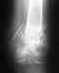

Здравствуйте, уважаемые форумчане.Нужно исправить левое бедро: увеличить длину на 4см и повернуть по оси на 15-20о. Очень не хочу ставить чрескостный аппарат. В бедре сейчас стоит штырь закрепленный только со стороны колена. Вопрос денег не так важен как вопрос времени комфорта и мобильности. Слышал что-то про телескопический стержень внутри кости, который удлиняется по мере надобности, мне что-то типа такого. Если это не фантастика, скажите куда обратиться?

Если интересно, расскажу предысторию. В 2004 году я получил открытый перелом. Из-за того что зашили рану плохо промыв, к моменту снятия швов перед плановой операцией там уже было загноение, которое лечили ровно 3 месяца. Естественно, к моменту операции образовалась сильнейшая контрактура в коленном суставе, которую во время операции "разработали" на 50%. Так же в месте перелома кусочки раздробленного бедра удалили и поставили кусок выпиленный из таза. Одели все обломки на штырь и закрепили болтами снизу и сверху. В последствии образовался ложный сустав, сняли верхние болты и верхний обломок под нагрузкой ходьбы "наделся" на штырь после чего нога и стала короче, но хотя-бы срослась.

Телескопируемый стержень в России легально не найти, они не зарегистрированы. Кроме того, это устройство стоит как автомобиль. И его применение может быть сопряжено со многими проблемами, как говорит опыт наших коллег, его применяющих.

Ваша проблема решается удлинением с помощью аппарата либо поверх стержня с немедленным снятием аппарата после достижения нужной длины, либо аппаратом с последующей его заменой на стержень. То есть в аппарате придется пробыть несколько недель. В нашем отделении есть немалый опыт такого рода операций.